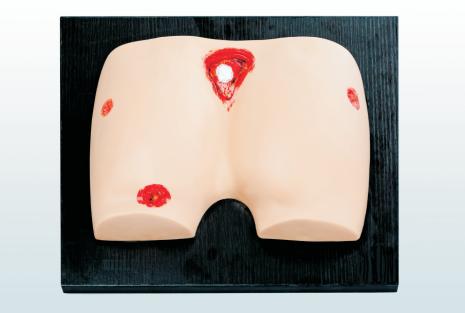

褥疮护理仿真模型

褥疮护理仿真模型

表面出血点止血训练模型

表面出血点止血训练模型